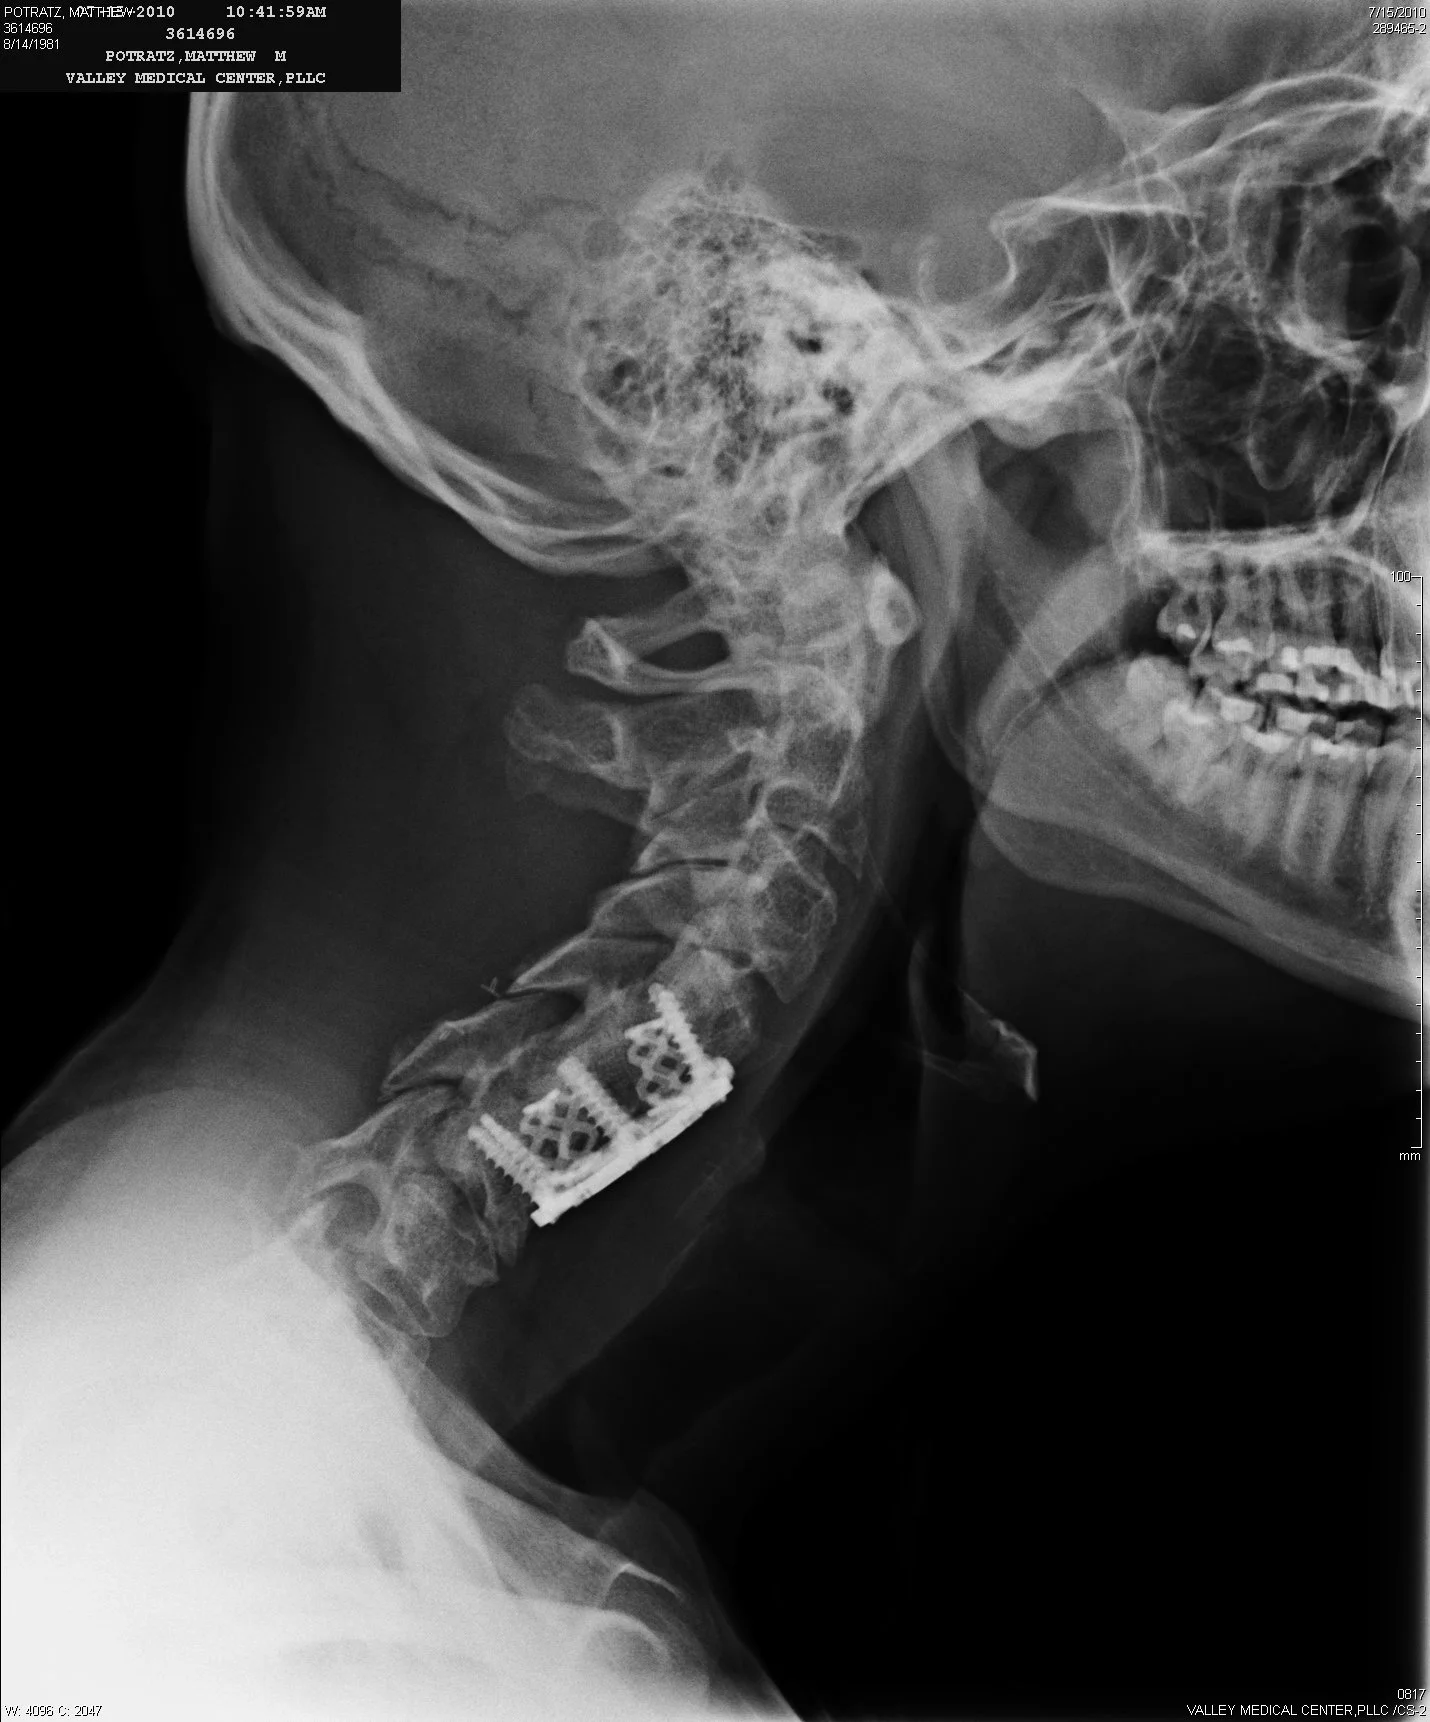

“From the time an avalanche fractured to the time I was violently crushed into a tree and buried, was twelve seconds. Life can definitely change in an instant. Everything had been going quite well for me, but in twelve seconds, I went from Hero to Zero.”